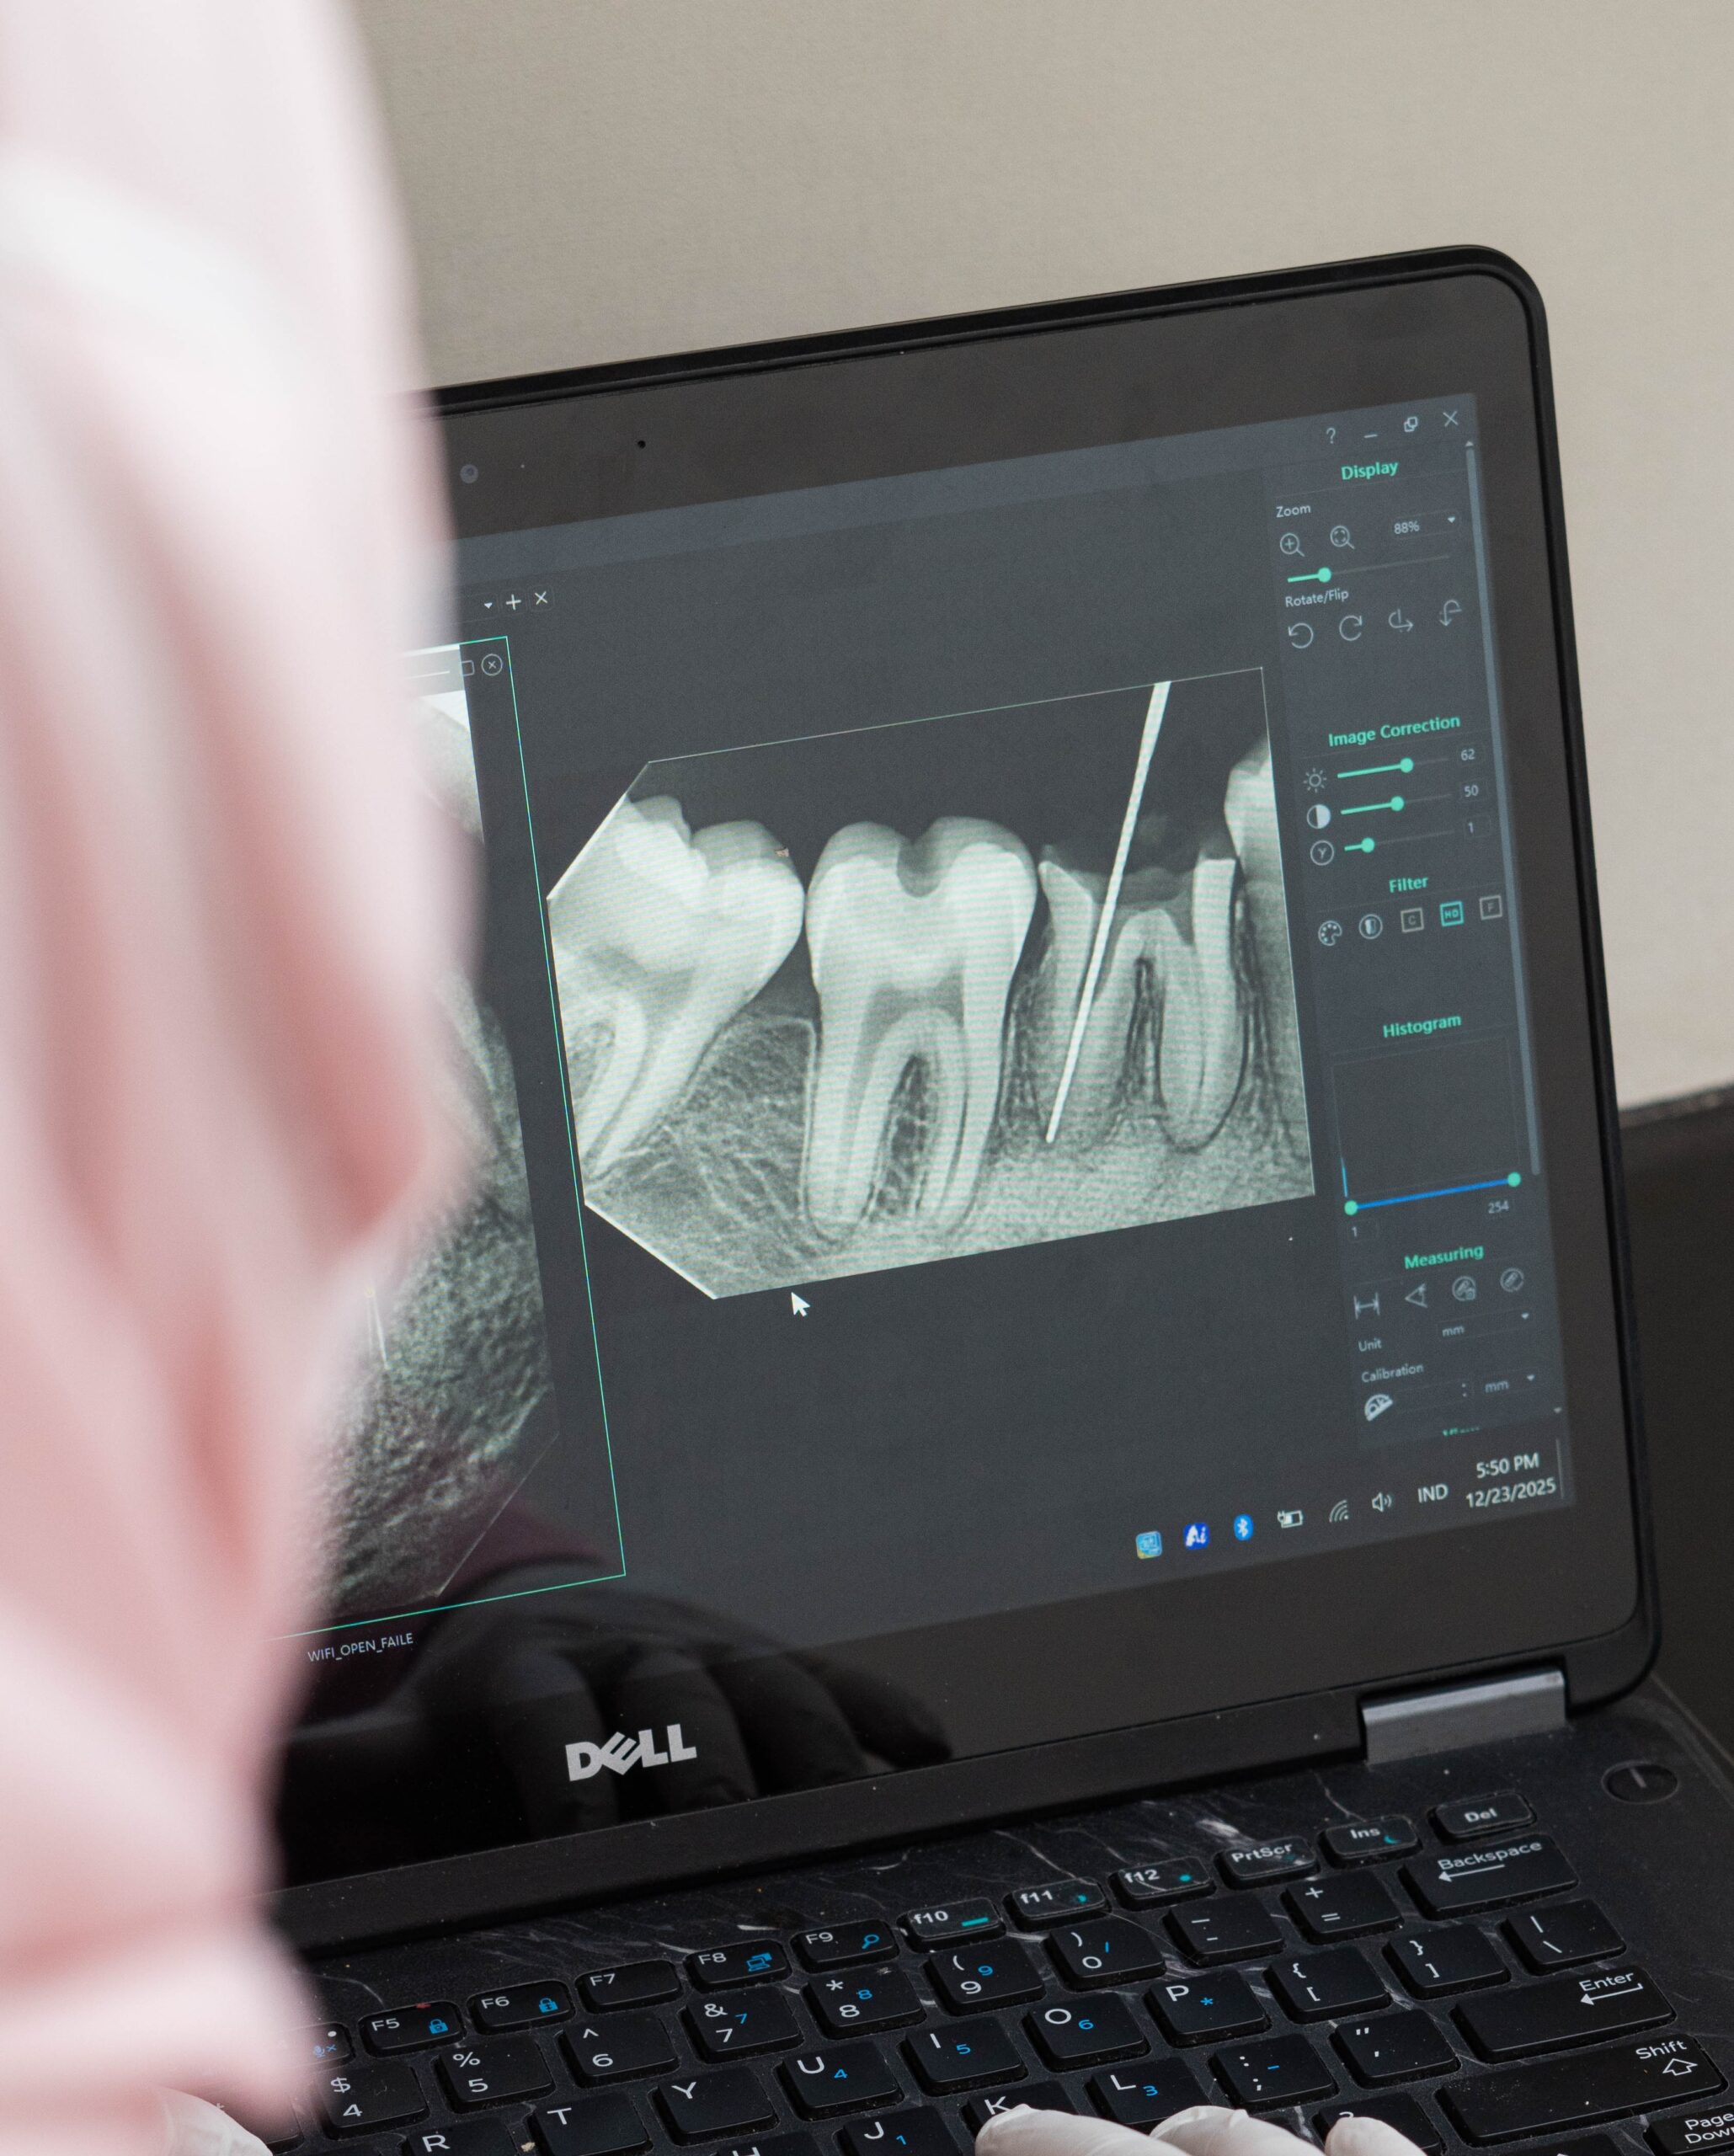

Perawatan Saluran Akar

Mengobati infeksi di dalam akar gigi agar tidak perlu dicabut.

Perawatan Saluran Akar

Mengobati infeksi di dalam akar gigi agar tidak perlu dicabut.